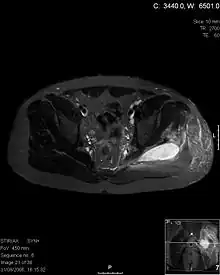

Axial T1 weighted fat suppressed post IV gadolinium contrast enhanced MRI image showing a mutliloculated bacterial abscess in the left gluteal muscle which grew Staphylococcus aureus (methicillin sensitive) thought to be due to tropical pyomyositis.

Coronal fat suppressed post contrast image showing a multiloculated bacterial abscess in the left gluteus minimus muscle due to tropical pyomyositis.

Coronal T2 weighted fat suppressed image showing a multiloculated fluid collection in the left gluteal musculature due to tropical pyomositis in a 12-year-old boy.